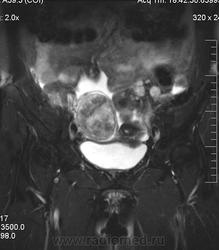

в-целом, cогласен. Карциноматоз тоже есть. Видится еще диффузный аденомиоз матки (задней стенки).

Мне кажется, что есть инфильтрация и передней стенки прямой кишки.